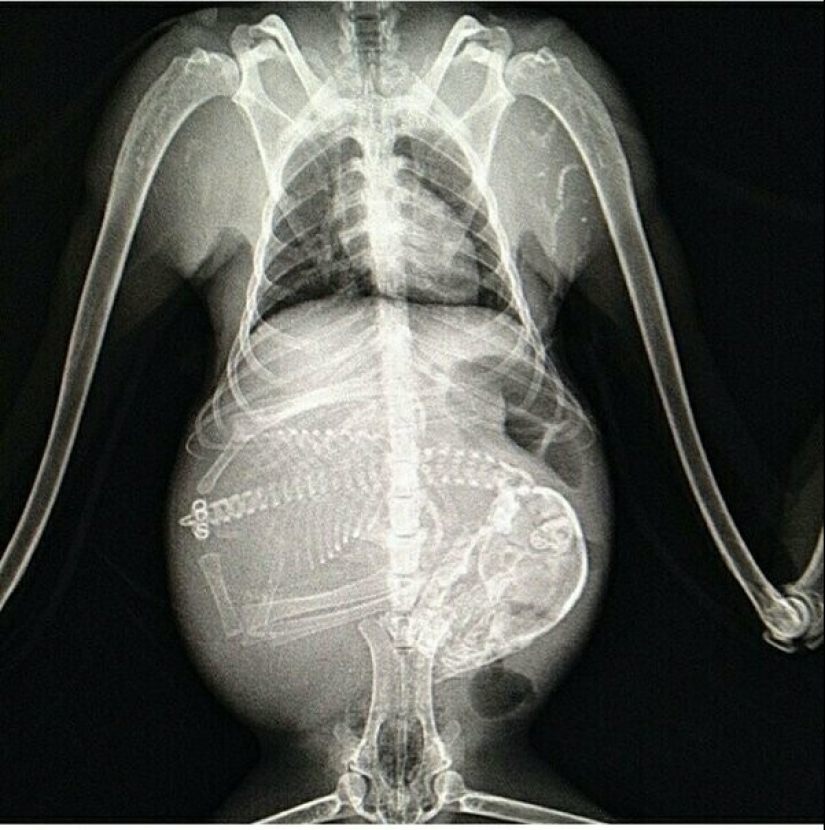

Pregnant monkey